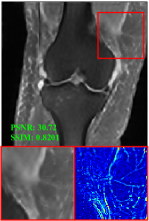

Figure 5 provides the qualitative comparison of the various methods on the four datasets at a scale of 4. The top, second, third, and bottom rows are the SR results under the FastMRI, clinical brain, clinical tumor and clinical pelvic datasets, respectively. The red boxes indicate the zoom-in region of complicated anatomical structures along with their corresponding error maps. Note that the brighter textures in the error maps, the lower the quality of the reconstructed images. As can be seen, compared to methods based on Transformers and CNNs, diffusion-based methods like DisC-Diff and DiffMSR (Ours) are capable of reconstructing high-realistic images with promising reconstruction metric scores (PSNR and SSIM). Nevertheless, while DisC-Diff can reconstruct high-precision MR images, it does not preserve the structure present in the original HR images, introducing some additional information that can affect medical diagnosis. In contrast, our method combines DM and PLWformer, which can preserve the original image’s structure while restoring high-frequency information.

In Table 1, we provide a comprehensive quantitative analysis, comparing our DiffMSR with other state-of-the-art MCSR methods on four datasets with a 4 upscaling factor. As we can see, our DiffMSR performs best among all comparison methods in terms of PSNR and SSIM metrics in all MRI datasets. Specifically, we notice that the performance of CNN-based methods is relatively poor as CNNs struggle to capture long-range dependencies. Although Transformer-based methods address some of the issues with CNNs, the ability of Transformers to reconstruct high-frequency details is limited, restricting further improvements in metrics. The DisC-Diff method based on DM achieves high metric values, as DM can generate some high-frequency details, but it also introduces unnecessary information. Our proposed DiffMSR combines the strengths of Transformer and DM, preserving the original image structure while maximizing the reconstruction of complicated anatomical structures, obtaining the best performance.

In this section, we present more visual qualitative comparisons. Figures 8, 9, 10, and 11 show the reconstruction results of each method in FastMRI, clinical brain, clinical tumor, and clinical pelvic, respectively. As can be seen, although DisC-Diff can reconstruct MR images with high-frequency information, it fails to preserve the structure and content of the original Target HR image effectively, resulting in image distortion. In contrast, our proposed DiffMSR can restore high-frequency information while preserving the structure of the original HR image, indicating the effectiveness of the joint use of DM and PLWformer.